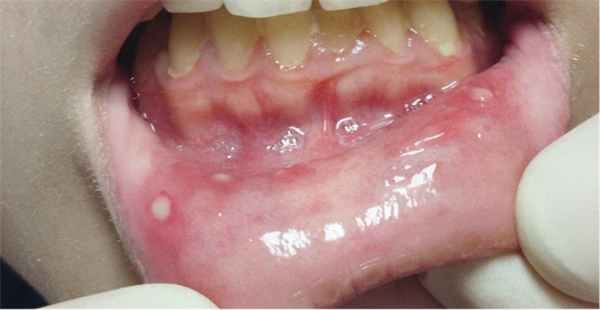

Афтозный стоматит — язвы обычно располагаются на внутренней стороне губ или слизистой оболочки щек, возникают примерно у 40-80% пациентов.

Афтозный стоматит - язвы располагаются на слизистой оболочки губ и щёк. Этот признак проявляется примерно у 40-80% пациентов.